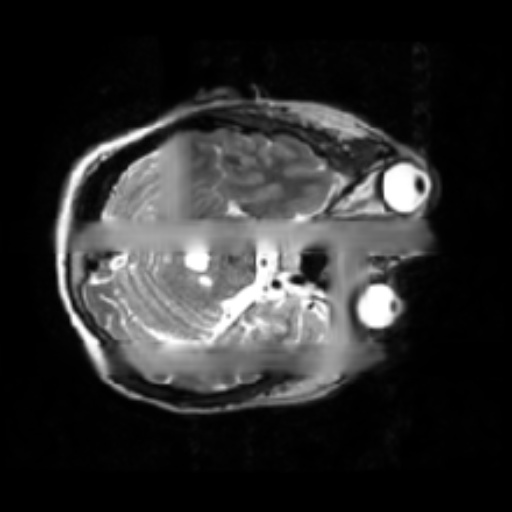

- 1.2 Examples of homogeneity in medical imaging modalities illustrating the similarity of the underlying subject (PET, CT, and MRI).

- (c) MRI of the brain1111footnotemark: 11

Thirdly, while seeming counter to the second point, while in a broad sense medical images are heterogeneous due to the very different imaging techniques and separation based on medical specializations (head scans vs foot scans), within a given data type, there is very high visual similarity. For example, all chest X-rays will look very similar due to standardized acquisition methods and tools, but also in large part, due to the high homogeneity of the human biology, see figure 1.2. For the chest scan example, most human bones and organs will have almost identical structures, similar sizes, and composition. Furthermore, the way these scans are collected is standardized, so the patients will all be positioned at the same angle and distance from the imaging machines. This is true even for data samples that have completely different labels, as the characteristics that indicate one diagnosis or another are often identified by very small, granular differences, which are visually very small in absolute terms. This poses a challenge to researchers in the sense that they can’t directly adapt many of the more recent and best-performing classes of Self-Supervised methods, such as contrastive learning. This has allowed us to develop methods that are tailored specifically for medical images.